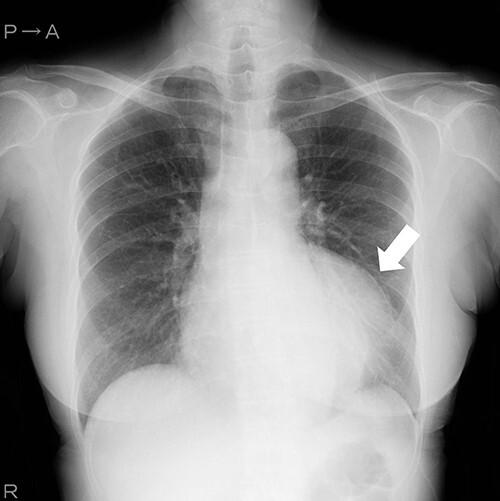

A rare case of giant coronary artery ectasia associated with coronary artery aneurysm was recognized. A 69-year-old woman presented with an ischemic electrocardiogram changes during a medical check-up. Coronary computed tomography angiography showed right coronary artery (RCA) ectasia associated with a giant aneurysm originating from the distal RCA. She was asymptomatic and exhibited no risk factors, including Kawasaki disease, hypertension, diabetes mellitus or family history. The patient underwent surgery for giant coronary aneurysms to prevent rupture. The aneurysm was on the peripheral side of the right coronary artery; hence, coronary artery bypass was not performed. The patient's postoperative course was uneventful. Histopathological examination of the aneurysm revealed degeneration due to atherosclerosis. She was prescribed warfarin and aspirin for thrombus prevention.

一例罕见的巨大冠状动脉扩张合并冠状动脉瘤被确诊。一名69岁女性在体检时出现缺血性心电图改变。冠状动脉计算机断层扫描血管造影显示右冠状动脉(RCA)扩张,伴有一个起源于RCA远端的巨大动脉瘤。她没有症状,也没有包括川崎病、高血压、糖尿病或家族史在内的危险因素。患者接受了巨大冠状动脉瘤手术以预防破裂。动脉瘤位于右冠状动脉外周侧;因此,未进行冠状动脉搭桥术。患者术后恢复顺利。动脉瘤的组织病理学检查显示为动脉粥样硬化性退变。她被开了华法林和阿司匹林以预防血栓形成。